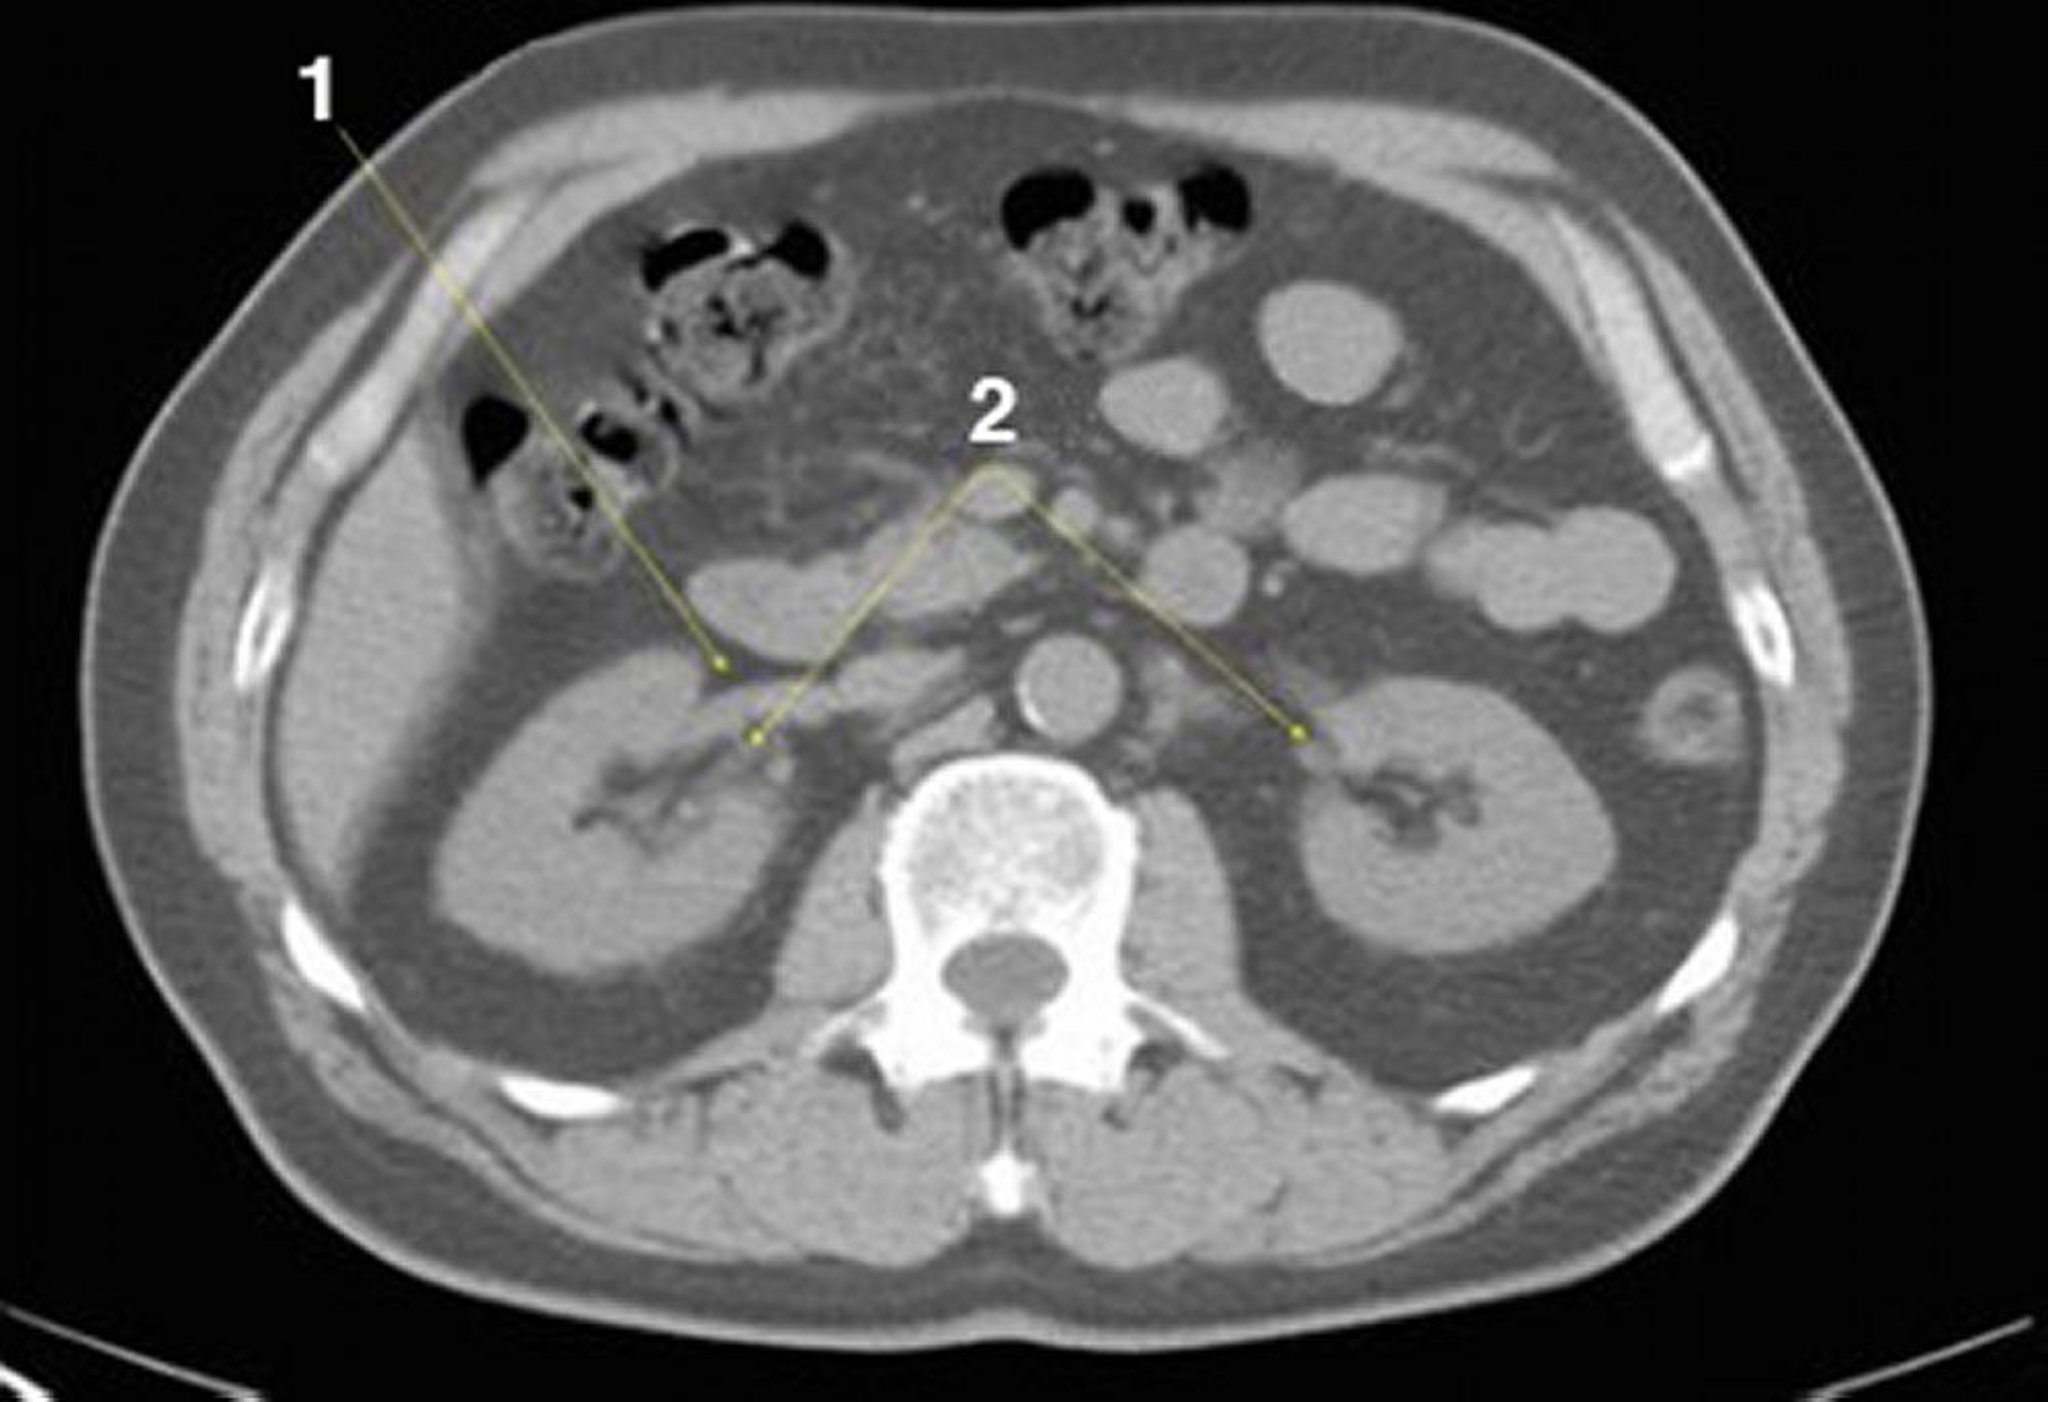

TC senza contrasto dell'addome e della pelvi che mostra un'anatomia normale (Slide 14)

1 = vena renale destra; 2 = reni all'ilo.